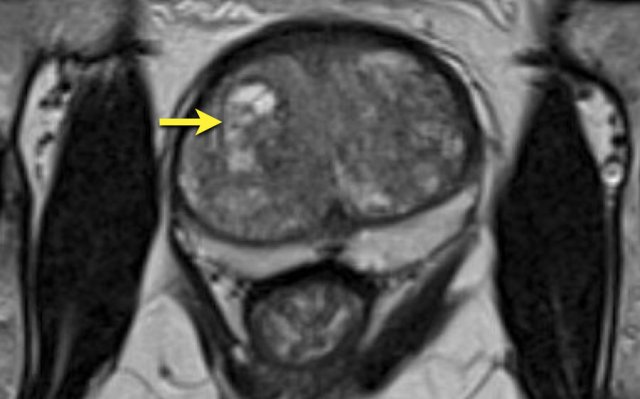

First look at the images and then continue reading.

The findings are:

- A lesion with PI-RADS assessment category 4 located in the left

peripheral zone in the mid-portion of the prostate.

Focal marked hypointensity on ADC (yellow arrow) (score 4), corresponding an hypointense area on T2W (score 4).

The Gleason score of this lesion was 3+4.

- A lesion with PI-RADS assessment category 3 is located in the right peripheral zone, with mild focal hypointensity on ADC (green arrow) with isointensity on DWI (score 3).

No DCE was performed and no further

discrimination could be determined.

Biopsy did not show any sign of

malignancy.